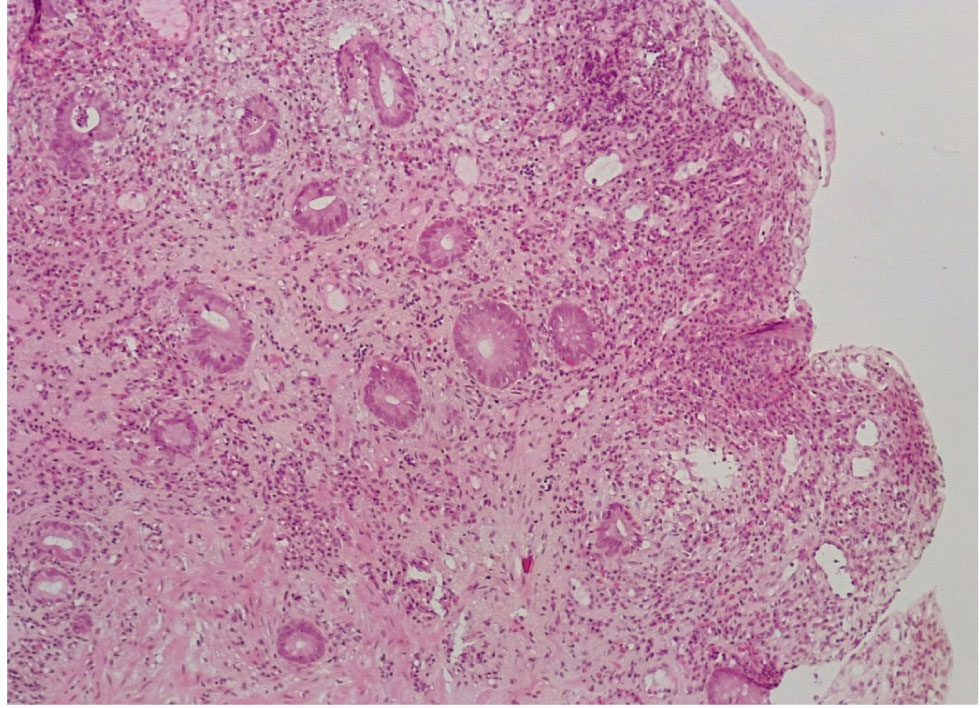

Окраска на слизь выявила почти полное исчезновение слизи на поверхности цилиндрического эпителия СО и в большинстве крипт за счет резко выраженной атрофии бокаловидных клеток (не более 4–5 БК на крипту) (+++) (рис. 5).

Рис. 5. Основная группа: снижение секреции муцина цилиндрическим эпителием СО толстой кишки, атрофия бокаловидных клеток и небольшое количество альциан + слизи в криптах. ШИК-реакция с докраской альциановым синим, ×200

В отдельных участках СО при НЯК встречались единичные крипты, содержащие отдельные бокаловидные клетки и альциан + гликопротеиды (нейтральные мукополисахариды), резко выраженное хроническое воспаление стромы с развитием рыхлой волокнистой соединительной ткани (фиброза) (+++ степень атрофии и фиброза) (рис. 6).

Рис. 6. Основная группа: в СО при НЯК отмечается резкая атрофия крипт и бокаловидных клеток, содержащих незначительное количество альциан + муцина. ШИК-реакция с докраской альциановым синим, ×200